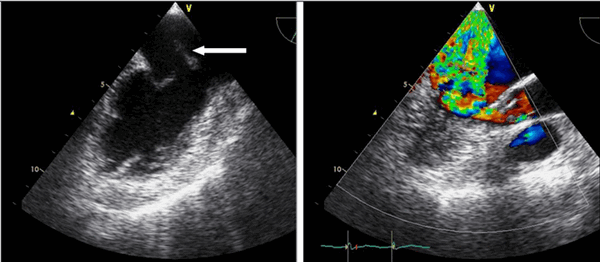

Так, например, эхокардиография с допплерометрией и цветным допплеровским картированием (ЦДК), которая является сочетанием 2D и М-режимов с допплерометрией, очень полезна при оценке митрального стеноза. Первые два способа визуализации позволяют заподозрить кальцификацию клапана (аномальное движение его створок).

- В двухмерном режиме можно детально визуализировать сам клапан, что позволяет определить наличие морфологических аномалий его структуры (кальциноз, пролабирование, патологическую подвижность, признаки ревматического поражения, эндокардита). На рисунке 6.1 показано ограничение подвижности стенозирован-ного митрального клапана у пациента.

- Цветовая допплерография позволяет провести полуколичественную оценку величины клапанной регургитации (легкая, средняя, тяжелая) на любом из клапанов сердца (митральном, аортальном, трикуспидальном или пульмональном).

В большинстве случаев ЭхоКГ назначается совместно с допплерографией (допплеровская ЭхоКГ), что позволяет в ходе одного исследования изучить как морфологию сердца, так и гемодинамическую значимость выявленных аномалий (например, при наличии шума митрального стеноза, когда с помощью двухмерной ЭхоКГ визуализируется малоподвижный, утолщенный и кальцинированный митральный клапан, а при допплерографии на основании анализа трансклапанной скорости кровотока и градиента давления определяется степень тяжести порока).